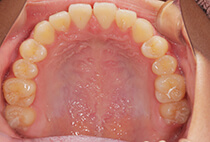

治療前

治療後

しっかり前歯を下げるために、インプラントアンカーを使用してコントロールしました。

かみ合わせが整うと咬筋の過緊張が改善。

過緊張による筋肉肥大も改善しフェイスラインもすっきりしました。